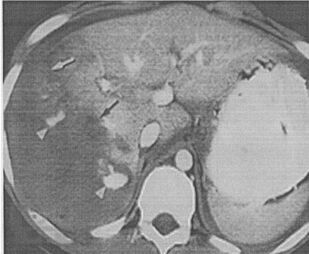

В пособии с современных позиций рассматриваются вопросы клинической и инструментальной диагностики травм печени и диагностическая ценность каждого из них. Сформулированы хирургическая тактика при травмах печени и критерии определяющие хирургическую тактику.